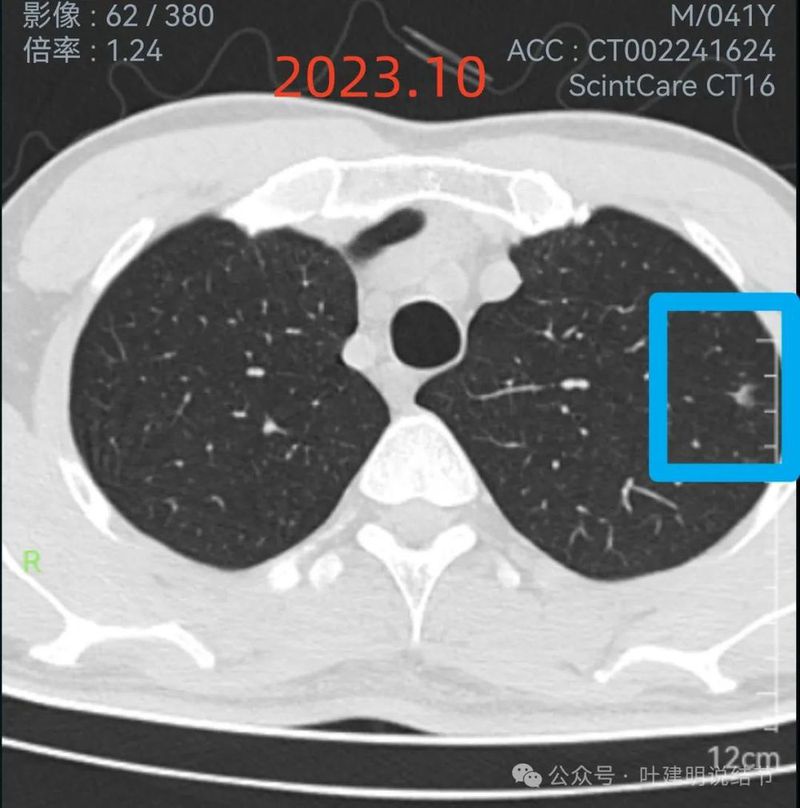

2023年10月时右侧病灶没有明显进展。

2023年10月时左侧病灶较前略明显,便仍觉得密度从高到低有移行,由于整体轮廓较前明显,恶性的可能性增加了。

红色的就是报告上所主要的病灶,右肺中叶的,这个病灶是磨玻璃结节,整体轮廓清楚,瘤肺边界也清,是要考虑是肿瘤范畴的。但是它密度低,没有实性成分,目前风险还不大,还没有到一定要干预的程度,或许在观察三年5年8年也不见得一定会进展。我的想法是再观察一下,半年到一年之间复查都可以。蓝色的界限欠清,实性部分密度过高,像炎性点。意见供参考!